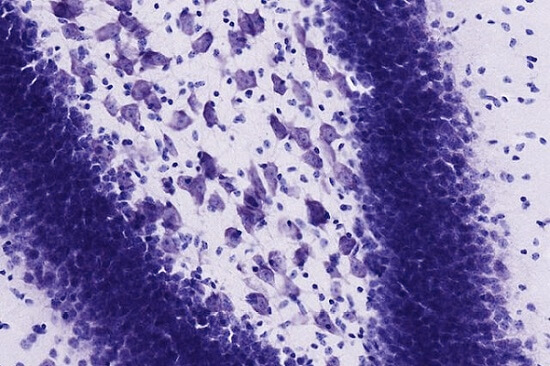

Los cuerpos de Nissl pueden observarse muy fácilmente en el microscopio óptico, ya que se tiñen selectivamente por su contenido de ARN.

Además del azul de metileno se utilizan otros muchos tintes para observar los somas de las células. El más usado es el violeta de cresilo. Esto ha permitido identificar masas de somas celulares, además de la localización de los cuerpos de Nissl.